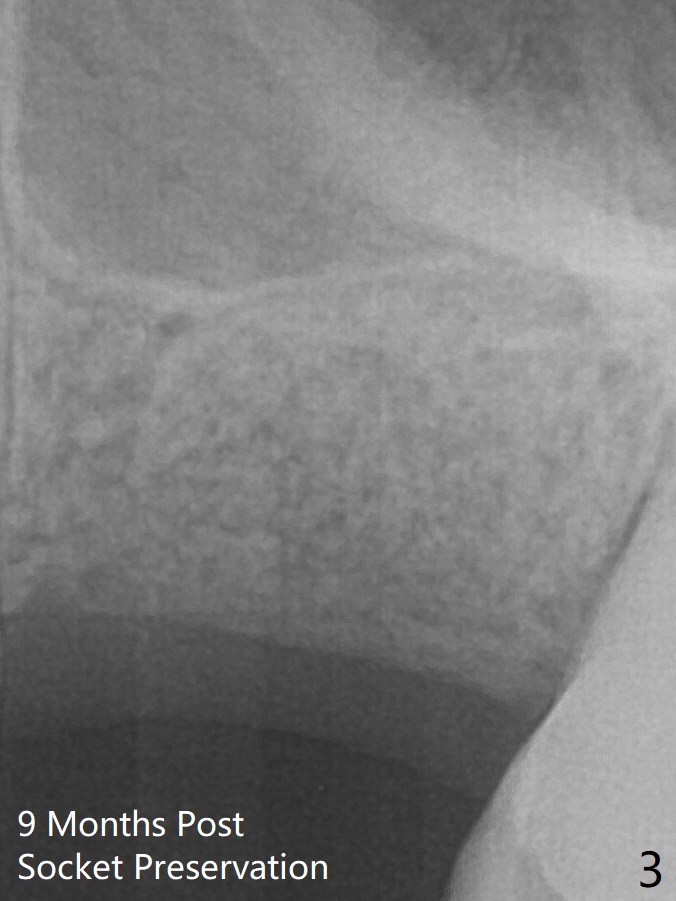

The patient returns 9 months post extraction/socket preservation (Fig.3). The ridge is wide at #14 11 months post socket preservation. Access and bone expansion (BEB) starts with Magic Split, followed by Magic Expanders 3.0, 3.8 and 4.3 mm from 8 to 9 mm for sinus lift. No bone is removed for osteotomy. Instead bone condensation occurs. After placement of a 4.5x11 mm dummy FC implant (Fig.1 with sinus lift), a 5x9 mm Magicore is placed with >55 Ncm with cuff margin at the gingival margin (Fig.2); a 5.5x3 mm solid abutment tries in. There is no occlusal clearance; trimming of the solid abutment will be needed.